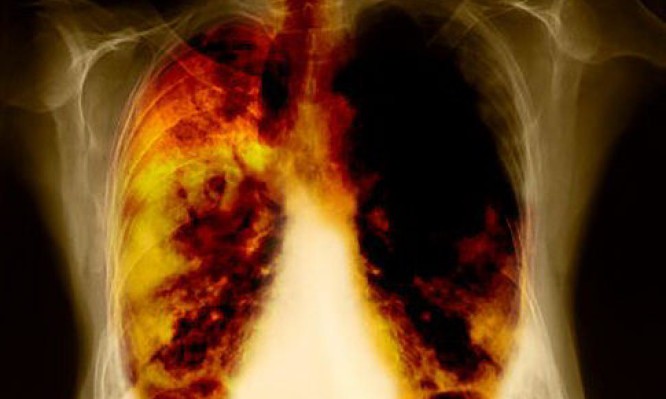

Γιατί μερικοί καπνιστές έχουν καθαρούς πνεύμονες

Πολλοί καπνιστές – αλλά όχι όλοι- θα αναπτύξουν κάποια πάθηση των πνευμόνων, όπως το ίδιο θα συμβεί και σε μερικούς που ποτέ δεν κάπνισαν στη ζωή τους. Η χρόνια αποφρακτική πνευμονοπάθεια (ΧΑΠ) προκαλεί δύσπνοια, βήχα και συχνές λοιμώξεις των πνευμόνων.

Η σύγκριση του DNA καπνιστών και μη, καθώς και όσων πάσχουν από ΧΑΠ και όσων όχι, έδειξε ότι σε μερικούς ανθρώπους υπάρχουν τμήματα του γονιδιώματός τους που μειώνουν τον κίνδυνο για την εμφάνιση ΧΑΠ. Έτσι, οι καπνιστές με αυτά τα «καλά» γονίδια έχουν μικρότερο κίνδυνο για ΧΑΠ, σε σχέση με όσους έχουν «κακά» γονίδια.

Όμως, όπως είπε ο Τόμπιν, «δεν φαίνεται να υπάρχει κάποιο είδος μαγικής σφαίρας που παρέχει στον οποιονδήποτε εγγυημένη προστασία έναντι του καπνίσματος – οι άνθρωποι αυτοί (σ.σ. με τα «καλά» γονίδια») θα συνεχίσουν να έχουν πνεύμονες λιγότερο υγιείς από ό,τι θα είχαν, αν δεν ήσαν καπνιστές».

Εκτός από την ΧΑΠ, το κάπνισμα αυξάνει τον κίνδυνο για καρκίνο των πνευμόνων και για καρδιοπάθειες. Μια άλλη διεθνής επιστημονική έρευνα, με επικεφαλής τον καθηγητή περιβαλλοντικής γενετικής Ντέηβιντ Κριστιάνι της Σχολής Δημόσιας Υγείας του Πανεπιστημίου Χάρβαντ των ΗΠΑ, που δημοσιεύθηκε στο ιατρικό περιοδικό «EbioMedicine», δείχνει ότι οι καπνιστές με ΧΑΠ έχουν σχεδόν διπλάσιο κίνδυνο να αναπτύξουν την πιο επιθετική μορφή καρκίνου των πνευμόνων.

Ο λεγόμενος «μικροκυτταρικός καρκίνος του πνεύμονα» αποτελεί το 15% έως 18% του συνόλου των καρκίνων των πνευμόνων παγκοσμίως και είναι η πιο θανατηφόρα μορφή. Παρά την αρχική θεραπεία, πολλοί ασθενείς υποτροπιάζουν μέσα σε ένα έτος. Το μέσο προσδόκιμο ζωής του ασθενούς είναι εννέα έως 20 μήνες μετά τη διάγνωση.